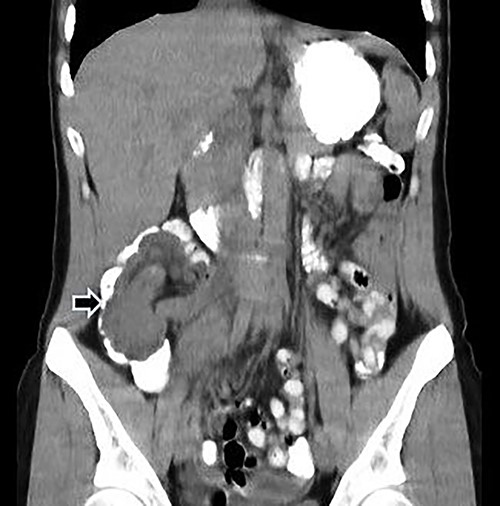

Computed tomography (CT) of the abdomen and pelvis with oral and intravenous contrast was performed (Fig. 1), and emergency surgery was decided due to the suspected ileocolic intussusception with a probable tumor origin (Fig. 2). The preoperative diagnoses were malignant cecum tumor (adenocarcinoma, sarcoma) or benign tumor (lipoma, villous tumor).

Abdominal CT with oral and IV contrast, axial view; tumoral mass and intussusception (arrow).